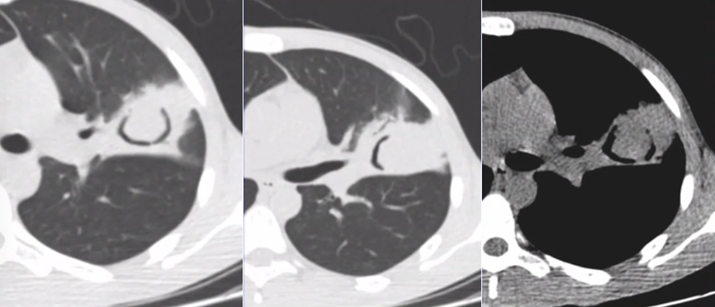

下图为一肿块,周围有晕征,中间有小气泡,增强扫描可见大片坏死,没有强化(图19),这种特征非常像曲霉感染,但最终穿刺病理证实为毛霉感染。其破坏范围更广。临床上,在诊断不清的情况下,一定要做增强扫描,能够帮助确定组织强化的程度。患者出现了胸腔积液,其中的小气泡更大,这是毛霉的特征。

图片

图19  毛霉感染

毛霉感染患者胸部CT可见反晕征,有胸腔积液,说明病变侵犯力非常强。其次,病变中的分隔粗大,其中的小气胞分布范围广。另外,病变中没有看到气液平面。但是由于病灶的破坏力更强更快,毛霉的生长跟不上,坏死物固定相对较弱,所以其病变破坏更多向外扩张,对血管的破坏性更大,因此我们看到很多低密度影。这是毛霉的特征。毛霉破坏组织后产生一些组织残留,因此CT上可见很多分隔(图20,图21)

图20  毛霉感染—反晕征,胸腔积液,分隔粗大

图21  毛霉感染—病变范围广、反晕征、胸腔积液